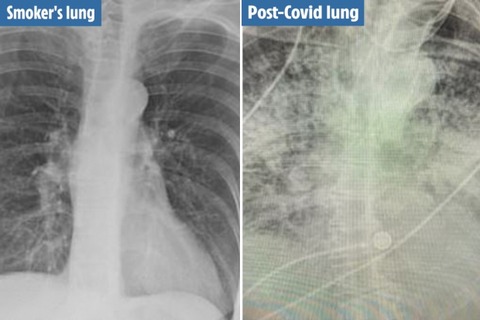

未分類 、SEV 【画像あり】コロナ感染者の肺のレントゲンがヤバイ事になっててワロタ… 2021年1月16日 2021年1月16日 54秒 negigasuki Facebook postはてブPocketFeedly 1: 以下、名無しにかわりましてネギ速がお送りします 2021/01/16(土) 05:16:29.859 ID:09k1Bo4K0 2: 以下、名無しにかわりましてネギ速がお送りします 2021/01/16(土) 05:16:54.607 ID:scquurC00 何が違うの? 20: 以下、名無しにかわりましてネギ速がお送りします 2021/01/16(土) 05:28:19.185 ID:/ZJwBMZFd >>2 あんたエラ呼吸だね 続きを読む Source: http://www.negisoku.com/index.rdf powered by Auto Youtube Summarize共有: Facebook で共有するにはクリックしてください (新しいウィンドウで開きます) Facebook クリックして X で共有 (新しいウィンドウで開きます) X いいね:いいね 読み込み中… 関連 Facebook postはてブPocketFeedly